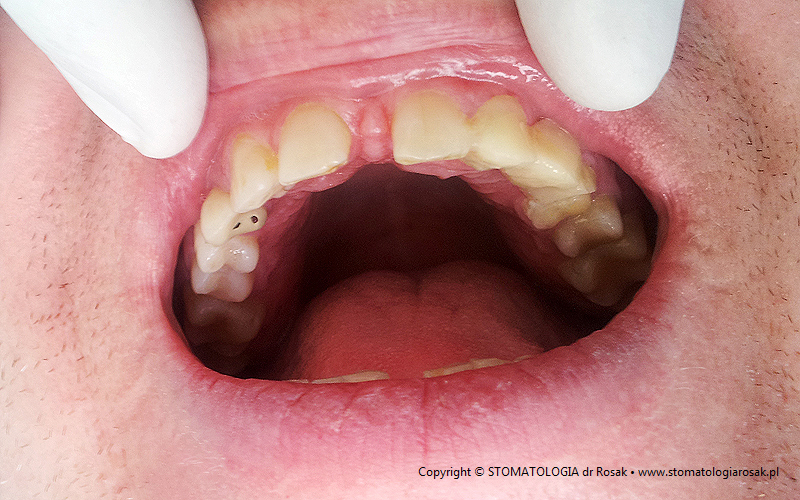

2. Pacjent z licznymi wypełnieniami (plombami), zgryzem głebokim, zaburzona estetyka

i funkcja układu narządu żucia (diastema).

| 2a. Pacjentka przed leczeniem |

2b. Gotowe mosty pełnoceramiczne

na podbudowie cyrkonowej |